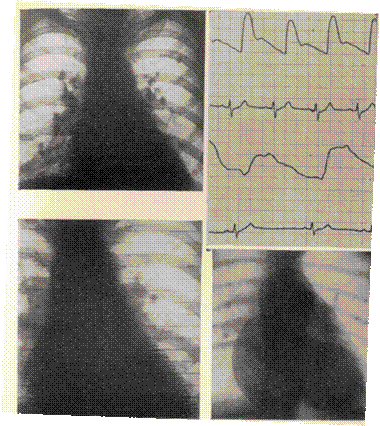

РЕНТГЕНОГРАММЫ БОЛЬНОГО СО СТЕНОЗОМ АОРТАЛЬНОГО ОТВЕРСТИЯ

Типичная аортальная конфигурация. Увеличение левого желудочка влево и кзади. Восходящая аорта расширена, а на рент-генокимограммах большие по амплитуде зубцы в этом отделе По дуге аорты зубцы уменьшены. На томограмме — обызвествление в области аортальных клапанов.